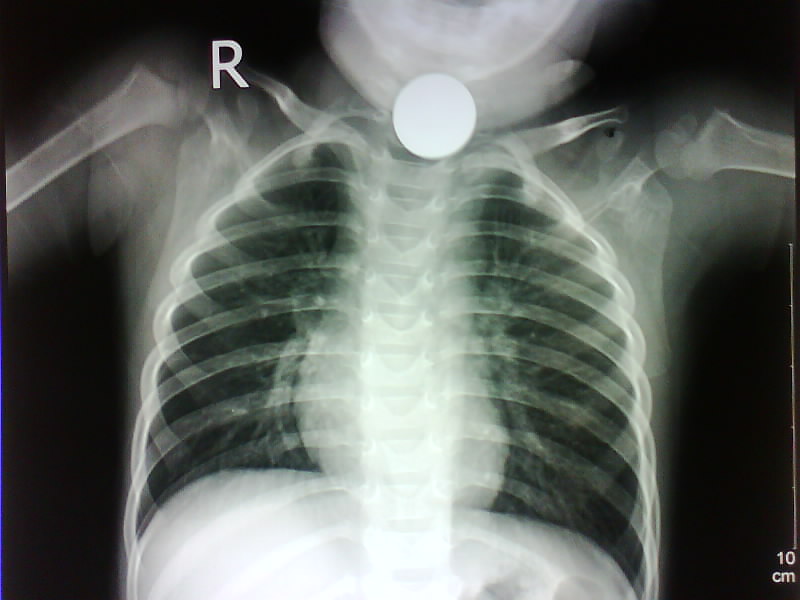

以下是引用随光逐影在2009-4-12 16:07:00的发言:[br]两肺尚清晰,心膈正常。[br]颈部体外异物?

以下是引用yrj0513在2009-4-12 18:42:00的发言:[br]结果:气管内异物(硬币),发帖的目的,是让战友们注意此问题.